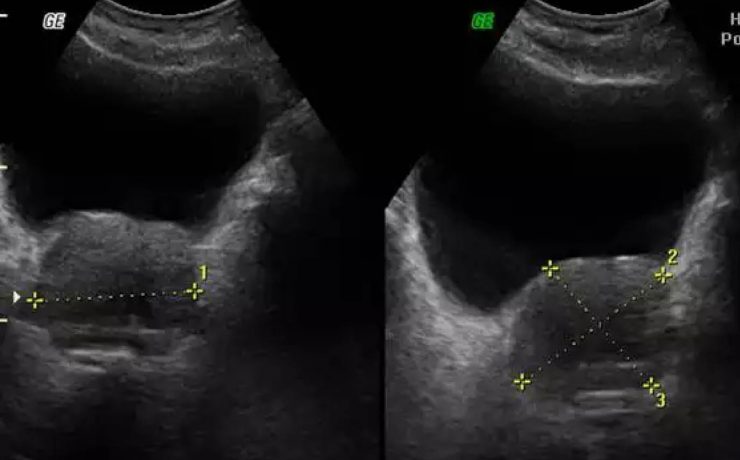

Patologías benignas de la próstata: prostatitis e hiperplasia prostática benigna.

Se realiza revisión detallada de la anatomía prostática y los principales factores que influyen en el aumento de volumen de la glándula prostática de origen patológico con diversas etiologías. Presentando como principales patologías la prostatitis y la hiperplasia prostática benigna. El término prostatitis incluye un conjunto de síntomas o disturbios